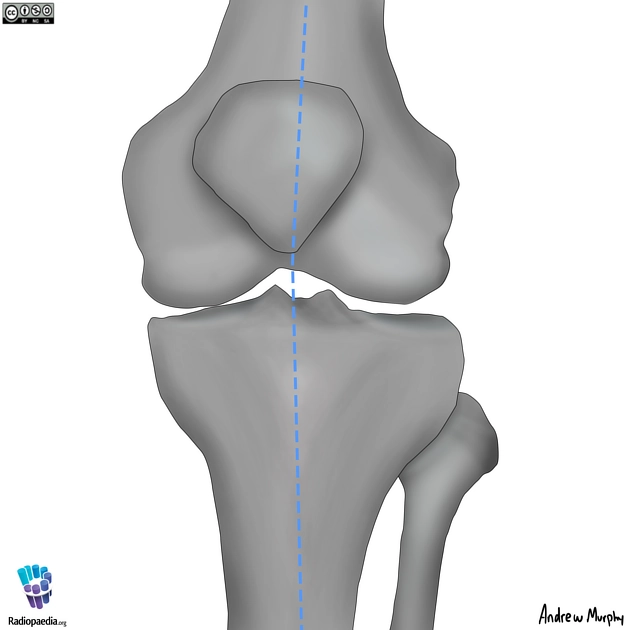

• Tổn thương xương và khớp gối

Gãy mâm chày (Tibial Plateau Fracture)